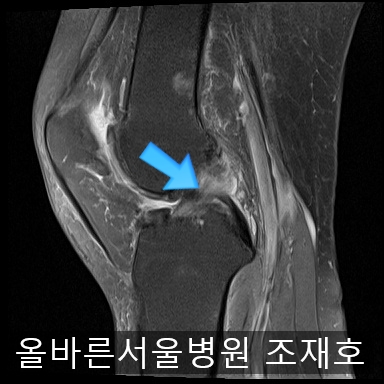

为了掌握具体情况拍了MRI。

虽然前方十字韧带粘液样变性,但稳定性无异常

后方十字韧带无明显异常。